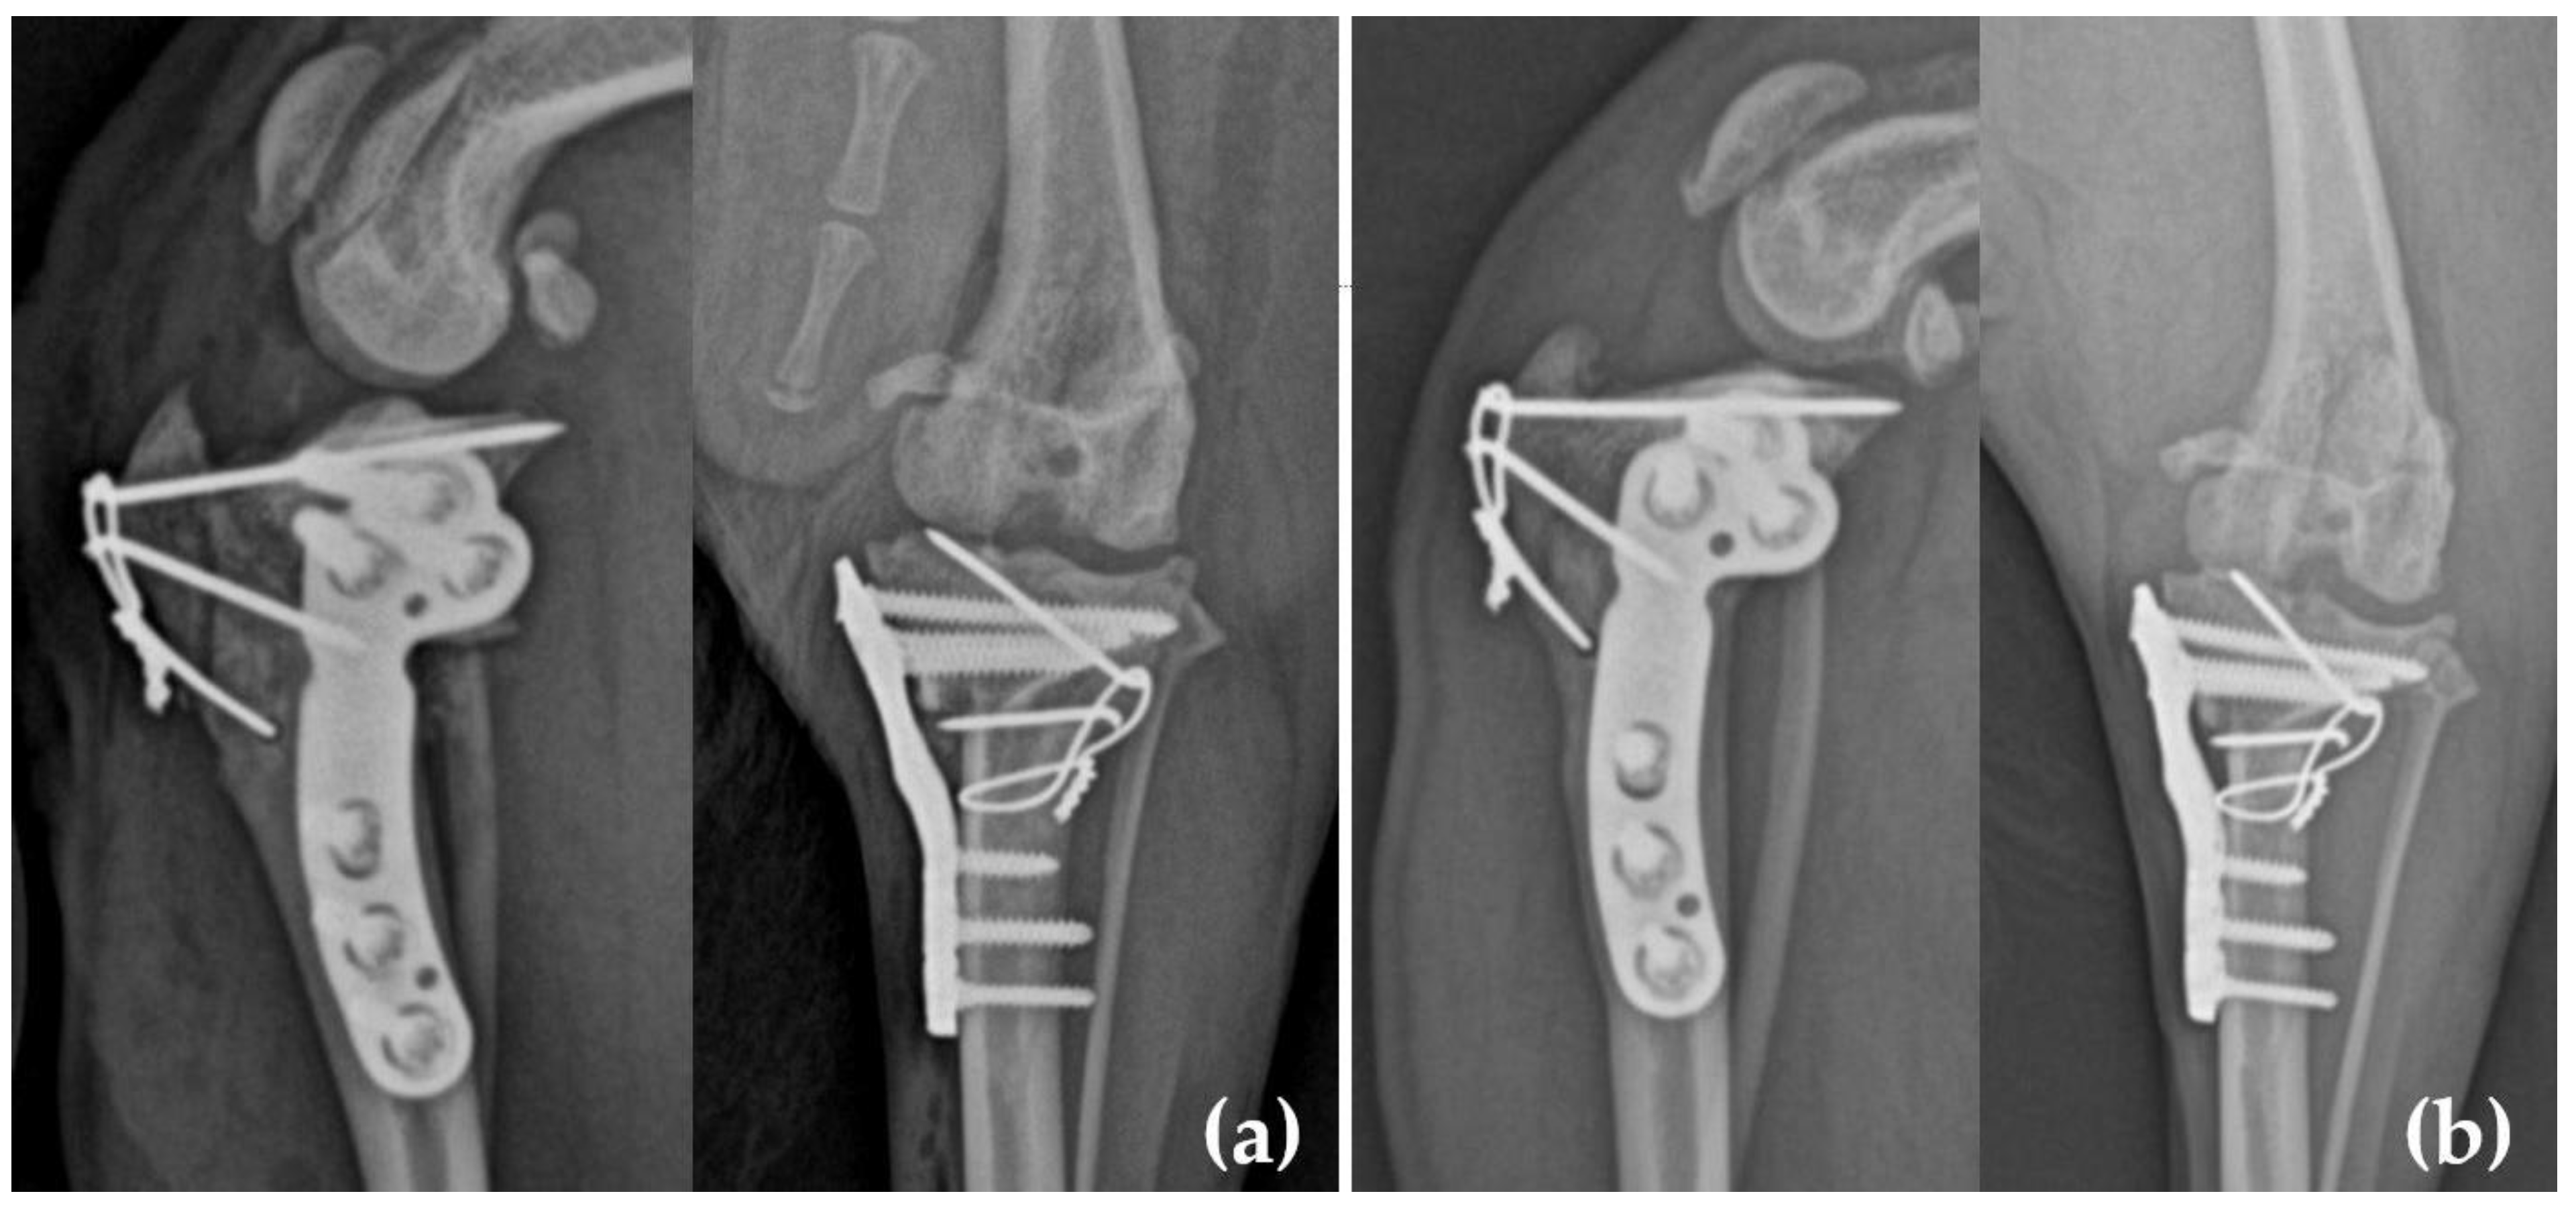

3.2. Surgical Procedures